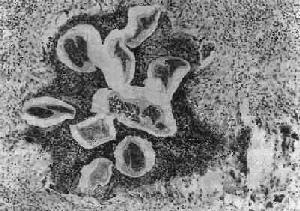

(1)淋巴管炎:多发生在较大的淋巴管,以下肢、精索、附睾、腹腔内淋巴管及乳腺等处较多见。肉眼观,急性期发炎的淋巴管呈一条红线样自上而下蔓延,形成所谓离心性淋巴管炎。当皮肤表浅微细淋巴管亦被波及时,局部皮肤则呈弥漫性红肿,称为丹毒性皮炎。镜下,常见淋巴管扩张、内皮细胞肿胀增生,管壁水肿增厚和嗜酸性粒细胞及单核细胞浸润。虫体死亡后对组织刺激强烈,引起凝固性坏死及大量嗜酸性粒细胞浸润,形成所谓嗜酸性脓肿。坏死组织中央可见死亡虫体断片及脱出在虫体外的微丝蚴,病变附近可找到Charcot-Leyden结晶。慢性期在脓肿周围出现类上皮细胞、巨噬细胞及异物巨细胞或Langhans巨细胞,形成结核样肉芽肿(图19-16)。随着虫体的钙化,肉芽肿逐渐纤维化,形成同心圆状排列的实心纤维索,使管腔完全闭塞,形成闭塞性淋巴管炎,而引起一系列继发改变。

图19-16 丝虫性淋巴管炎

图中可见数个切断的死虫体,周围有嗜酸性脓肿及肉芽肿反应